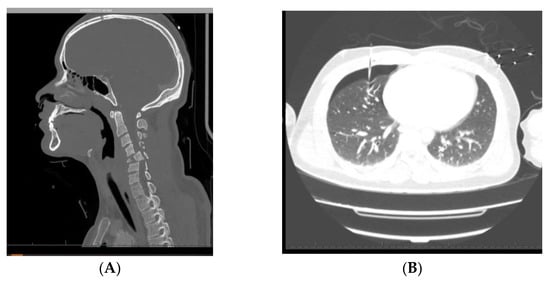

6.1. Case 1

6.2. Case 2